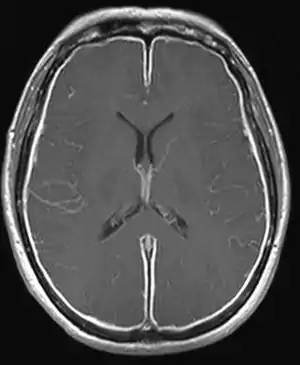

Meningite asséptica ou meningite estéril é uma condição na qual existe uma inflamação das camadas que revestem o cérebro, as meninges, mas que não é causada por bactérias piogénicas.[1]